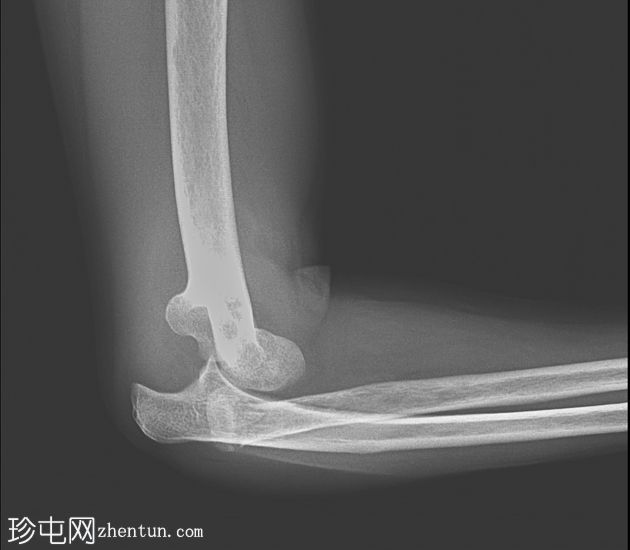

X线片

侧位

桡骨和尺骨相对于肱骨远端后脱位

桡骨颈横行骨折,桡骨头骨折块轻度移位

肱骨远端或冠突未见明显骨折

周围软组织肿胀和关节积液